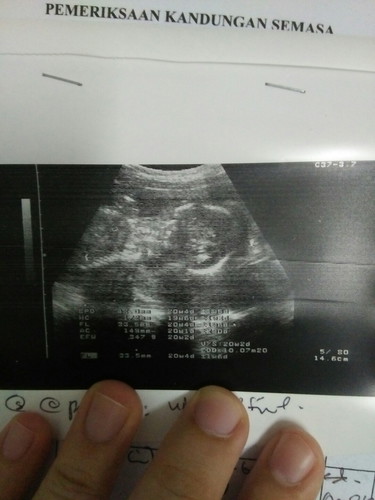

hai mamy² nak tanya ni kepastian lagi ada yg pandai tengok tak sbb doctor takda explain ba kat saya jadi saya tak pasti dia cuma ckp baby boi jadi saya tak dapat tengok time dia kena scan cuma gambar nya sak saya pun tak pandai tengok, korang tau tak baby boii atau girl dlm gmbar ni sis pun x brapa pasti klu doktor tu kata baby boi ?

if you want to know the gender, gambar scan ni tak boleh nak kenal pasti kalau boy or girl. if mommy nak tahu gender, buat gender scan tak pun ask for gambar scan dari celah kangkang.

Sis kena bayar lain utk scan gender scan.. Mungkin masa scan ni doc trnmpk burung dia.. So dia ckp boy.. Kalau nk gmbr gender scan, position dia lain..

Dt gmbr ni , nmpk kepala n tulg blkg dia je. Biasa klu nk tgk jntina, msti view dari celah kelangkang dia, btween kedua tulang peha

Yg dlm gambar scan tu rasanya bukan part gender dia. Macam bahagian kepala dan badan. So tak nampak mana gender dia 😅

Mungkin masa doc tengah belek2 baby dkt skrin tu dia nampak jantina baby kot. Yg print tu memang tak nampak bahagian jantina baby 😅

😂😂 ini kepala tulang blkg baby. Pandangan dari tepi... Sya pun x tau boy kah girl..

Mgkn masa scan doc scan area bawah... Yg ni doc ambil atas badan. Nnt next scan minta doc scan jantina bg cnfrm.. tp klu doc blg boy mmg boy la tu